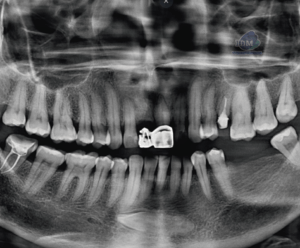

Paciente femenino de 53 años acude para una evaluación general. A la evaluación de la tomografía volumétrica (cone beam) bimaxilar en los cortes axiales (Figura 1) y tangenciales (Figura 2) se observa que adicional al foramen entoneano de lado derecho la presencia de dos forámenes accesorios de menor calibre uno mas hacia medial y el otro hacia caudal.

CORTES TANGENCIALES